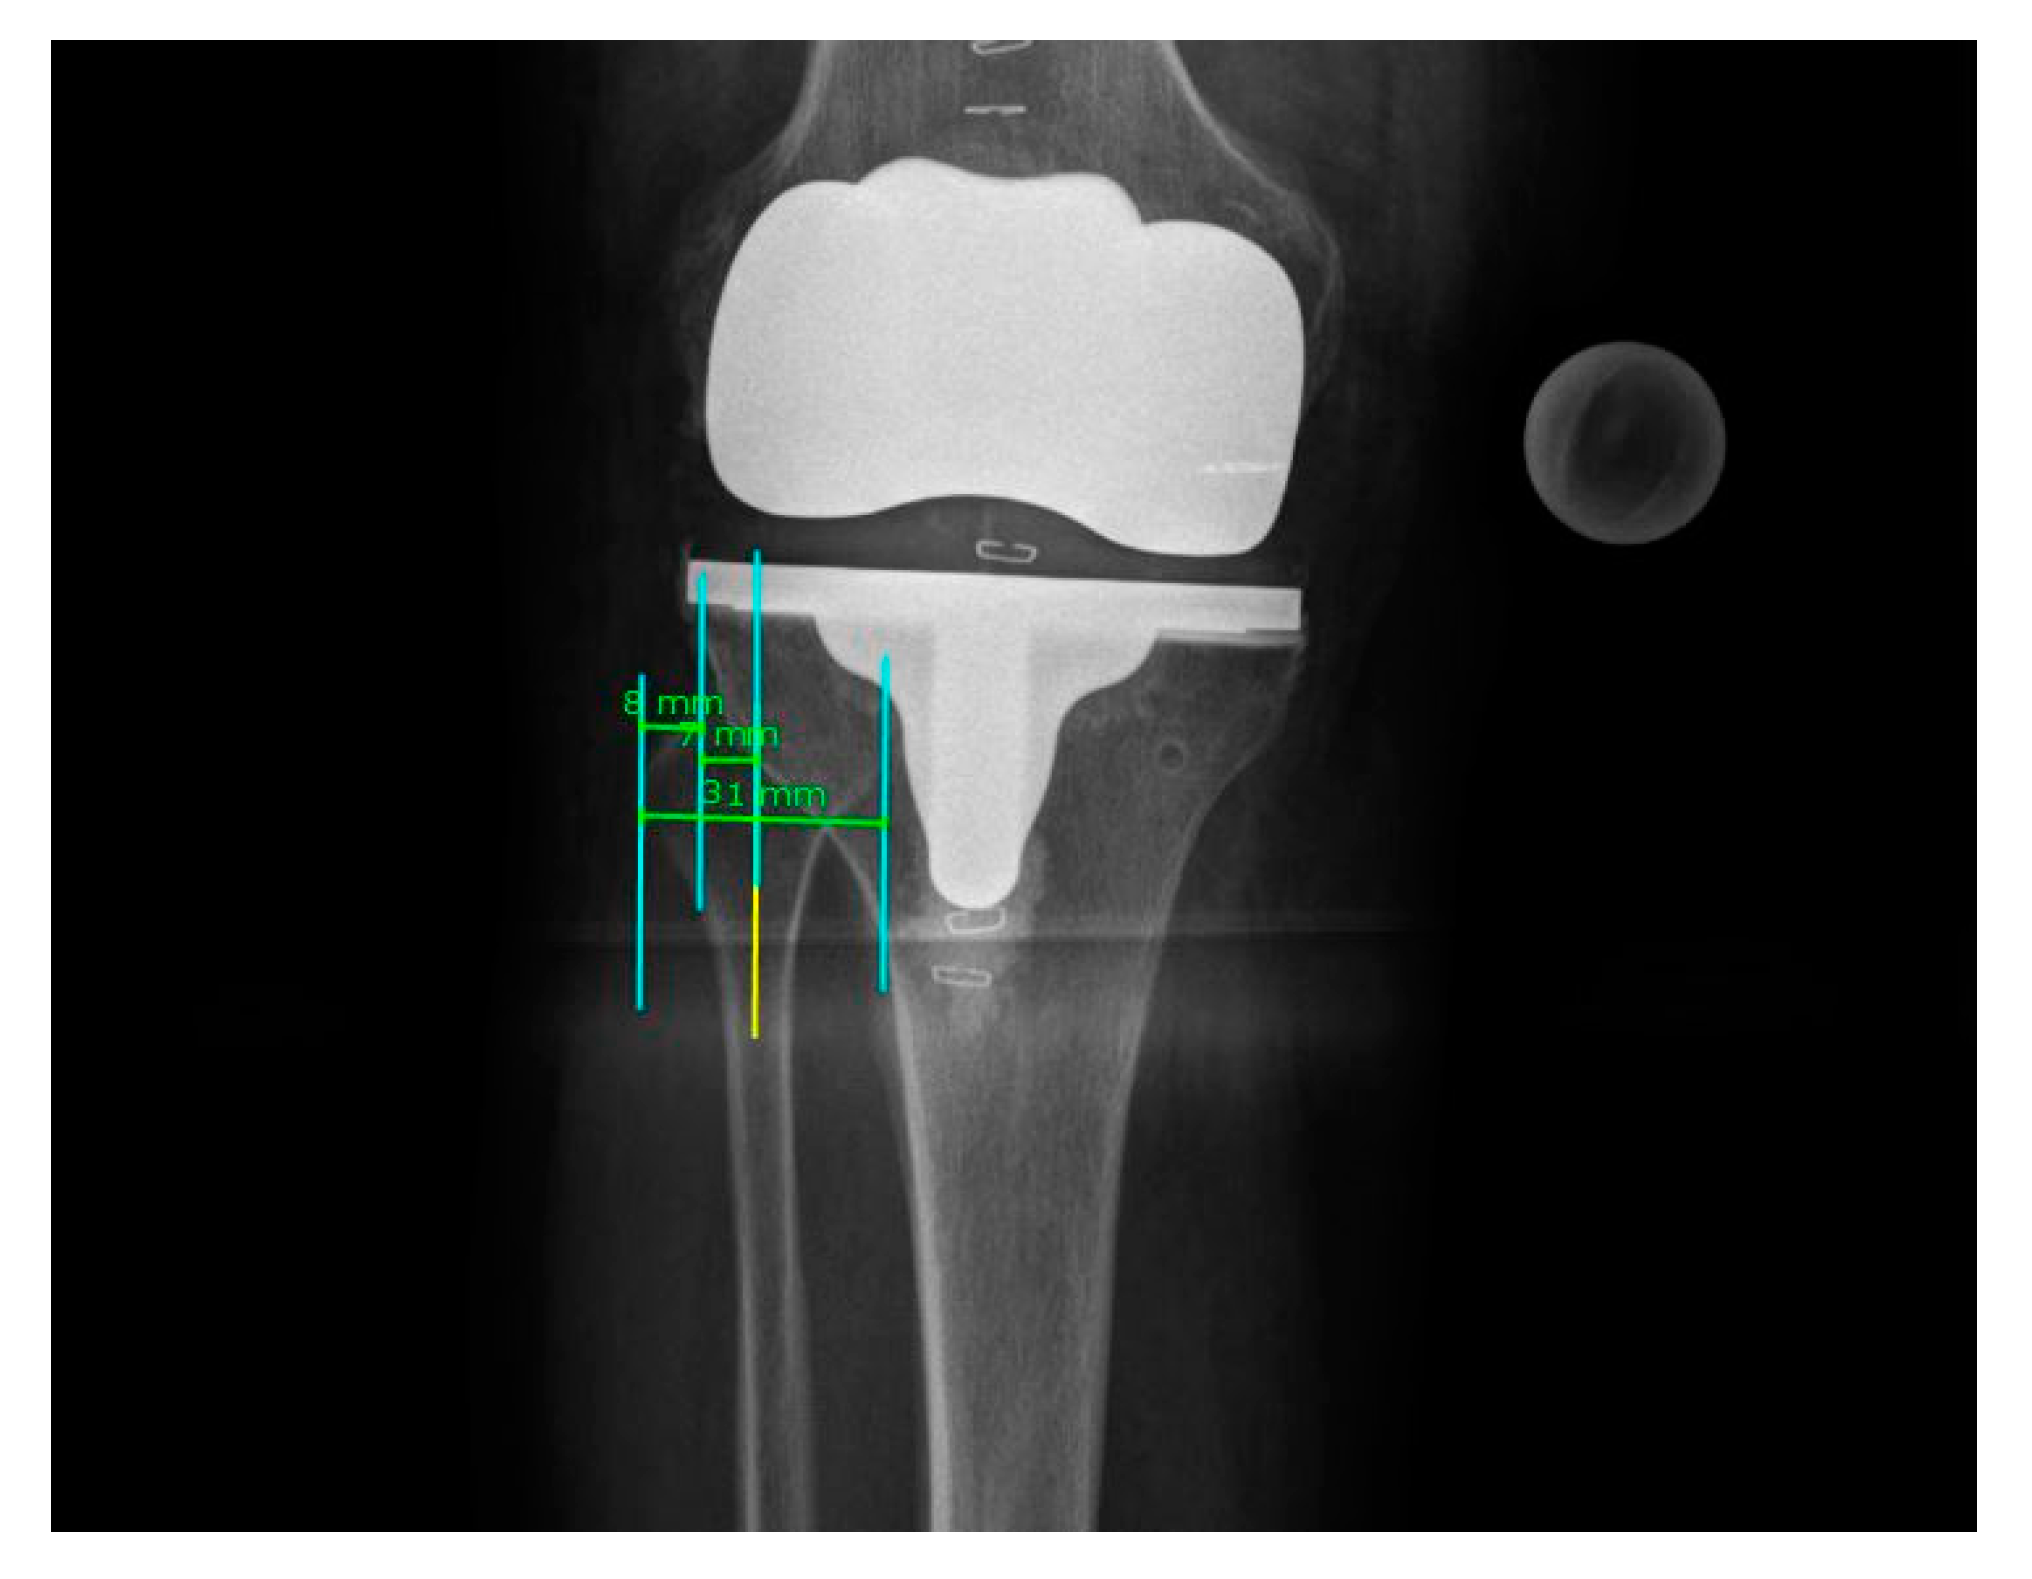

- Maderbacher, G.; Schaumburger, J.; Baier, C.; Zeman, F.; Springorum, H.-R.; Dornia, C.; Grifka, J.; Keshmiri, A. Predicting knee rotation by the projection overlap of the proximal fibula and tibia in long-leg radiographs. Knee Surgery, Sports Traumatol. Arthrosc. 2014, 22, 2982–2988. [Google Scholar] [CrossRef] [PubMed]

- Maderbacher, G.; Matussek, J.; Greimel, F.; Grifka, J.; Schaumburger, J.; Baier, C.; Keshmiri, A. Lower Limb Malrotation Is Regularly Present in Long-Leg Radiographs Resulting in Significant Measurement Errors. J. Knee Surg. 2021, 34, 108–114. [Google Scholar] [CrossRef] [PubMed]

- Maderbacher, G.; Baier, C.; Benditz, A.; Wagner, F.; Greimel, F.; Grifka, J.; Keshmiri, A. Presence of rotational errors in long leg radiographs after total knee arthroplasty and impact on measured lower limb and component alignment. Int. Orthop. 2017, 41, 1553–1560. [Google Scholar] [CrossRef]